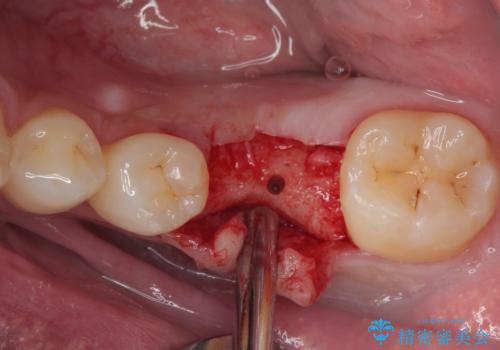

インプラント部は埋入とともに仮歯を装着し、同時に上顎奥歯の部分矯正を開始することとしました。

- 外科手術のため、術後に痛みや腫れ、違和感を伴います